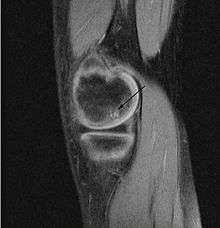

Magnetic resonance imaging (MRI) is useful for staging OCD lesions, evaluating the integrity of the joint surface, and distinguishing normal variants of bone formation from OCD by showing bone and cartilage edema in the area of the irregularity. MRI provides information regarding features of the articular cartilage and bone under the cartilage, including edema, fractures, fluid interfaces, articular surface integrity, and fragment displacement.[36][37] A low T1 and high T2 signal at the fragment interface is seen in active lesions. This indicates an unstable lesion or recent microfractures.[29] While MRI and arthroscopy have a close correlation, X-ray films tend to be less inductive of similar MRI results.[37]